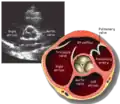

Parasternal short axis (PSAX)

This view is obtained in the same window as the parasternal long, but with the probe rotated 90°. In this view, the aortic valve is seen in cross-section with the right ventricular inflow & outflow tracts visible with the tricuspid valve as well. Pulmonary valve is not visible in this view. Both the right and left atria are visible.

The standard PSAX view is at the level of the aortic valve, but moving the probe along the long-axis can review the LV outflow tract, LV at the base, and LV at the midsection.

- Aortic valve in short-axis

- Aortic valve dysfunction, aortic sclerosis/stenosis